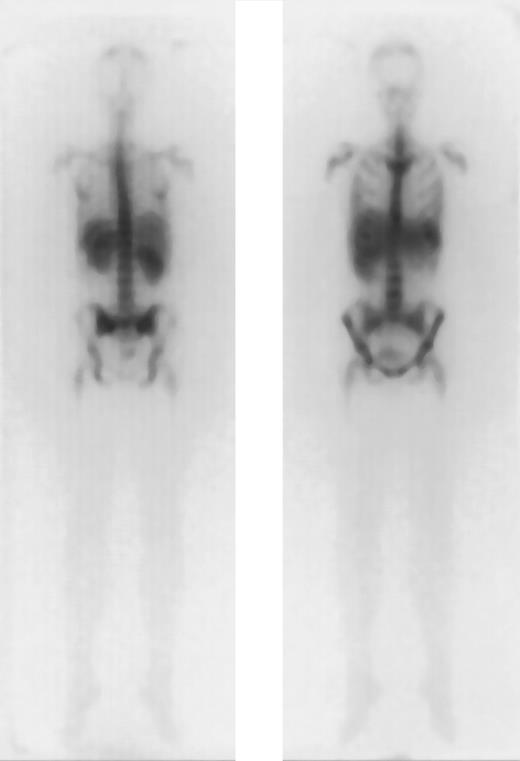

The results of dosimetry for some of these patients have been previously published.37 The tracer dose consisted of 1 to 2 mg anti-CD66 antibody labeled with 1.2 ± 0.6 GBq188Re. The application of the tracer dose was tolerated without any significant reaction by all 36 patients. All of these patients had a favorable dosimetry as defined above and proceeded to transplantation. For therapy a mean of 11.1 ± 2.2 GBq was injected in 1 to 2 fractions. A typical example is given in Figure1. The detailed results of dosimetry are shown in Figure 2 and Table2. The total doses shown in Table 2include the radiation exposure due to the dosimetric dose. The mean red marrow dose achieved was 15.3 ± 4.8 Gy, and the median dose was 14.9 Gy, ranging from 8.1 to 28 Gy. The kidney was the normal organ receiving the highest dose in 22 patients; the liver in 10 patients; and equivalent doses to kidney and liver were observed in 4 patients. Thus, the radiation absorbed doses were red marrow, 1.5 ± 0.6; spleen, 1.6 ± 1.3; liver, 0.5 ± 0.2; kidney, 0.7 ± 0.2; and lung, 0.1 ± 0.1 Gy/GBq. These values therefore give the following marrow:organ ratios: marrow:liver, 3:1; marrow:kidney, 2.1:1; and marrow:lung, 15:1. We observed no significant differences between the marrow doses of patients in complete remission and those in PR. The acute toxicity of the therapeutic antibody application was very mild, with two-thirds of patients complaining of mild nausea; no episodes of severe toxicity were observed.

Favorable dosimetry in a patient with AML in PR (unique patient number 664).

Biodistribution of 1 mg 188Re-labeled anti-CD66 monoclonal antibody after 40 hours, in anteroposterior and posteroanterior projection.